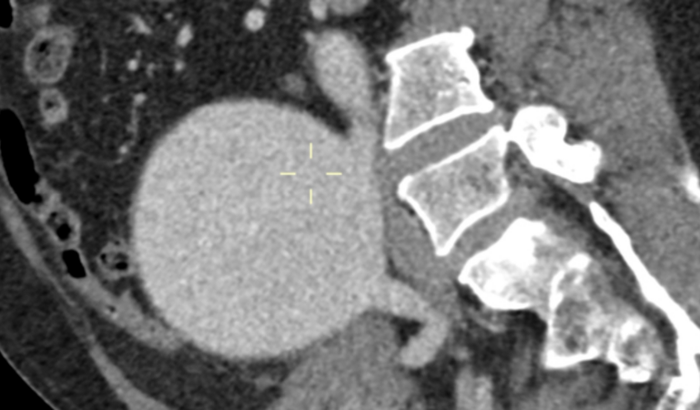

Oi, me chamo Palloma Cristinne de Castro Bastos. Descobrimos recentemente que meu paizinho, Albino Bastos, está com um Aneurisma da Aorta Abdominal (AAA) e precisa de uma cirurgia de urgência.